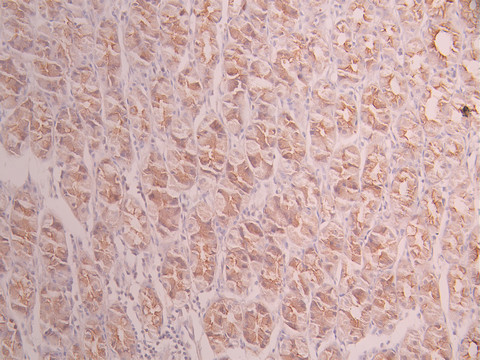

IHC image of CSB-RA598178A0HU diluted at 1:100 and staining in paraffin-embedded human breast cancer performed on a Leica BondTM system. After dewaxing and hydration, antigen retrieval was mediated by high pressure in a citrate buffer (pH 6.0). Section was blocked with 10% normal goat serum 30min at RT. Then primary antibody (1% BSA) was incubated at 4°C overnight. The primary is detected by a Goat anti-rabbit polymer IgG labeled by HRP and visualized using 0.05% DAB.